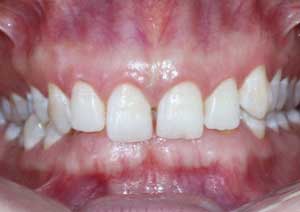

La supraclusion est définie comme le recouvrement excessif des incisives mandibulaires (inférieures) par les incisives maxillaires (supérieures).

Cliniquement, cela signifie qu’au sourire, le patient ne laisse pas apparaître les dents inférieures.

Il s’agit d’un problème de dimension verticale, fréquemment rencontré en pratique orthodontique quotidienne.

Le traitement de la supraclusion : Le traitement de la supraclusion repose avant tout sur un diagnostic précis, permettant de déterminer son origine dento-alvéolaire, squelettique ou mixte, ainsi que l’âge du patient.

Les objectifs principaux sont de réduire le recouvrement incisif, de rétablir une dimension verticale équilibrée et d’assurer une fonction occlusale stable.

Avant